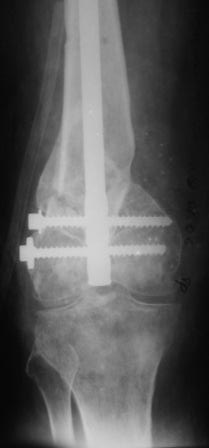

Anton Kovalenko 01 Февраль 2006, 00:42

Уважаемые коллеги! Представляю на ваш суд ближйший результаты лечения.

Первое что пришло в голову по аналогии очень похоже на асептический некроз головки бедра когда головку извлекают при эндопротезировании.Хрящ внутреннего мыщелка бедра был отслоен и изменен,сам мыщелок проминался под пальцем. От блокирования стяжкой отказались. Можно ли это расценить как асептический неркоз внутреннего мыщелка в результате первичной травмы?

Леонид Соломин писал о случае с пателлофеморальным синдесмозом(спасибо), но к сожалению сообщение пришло уже после операции.Прежде мы не встречались с подобным.Во время мобилизации после артролиза, отсечения интремедиуса попытались согнуть колено: хрящ надколенника остался на мыщелках бедра(!). В результате приняли решение удалить надколенник.

Раннее послеоперационное течение не очень спокойное- из раны было сукровичное отделяемое, но сейчас вроде идет на поправку(на фоне интенсивного лечения). В аттаче рентгенограммы.

Рентгенограмма симпатичная...